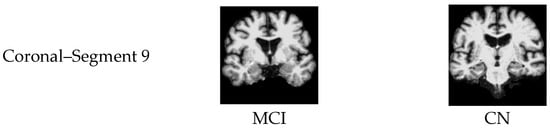

| Segment 9 | 94.3 | 95.4 | 92.9 | 94.1 | 95.7 | 98.5 | |